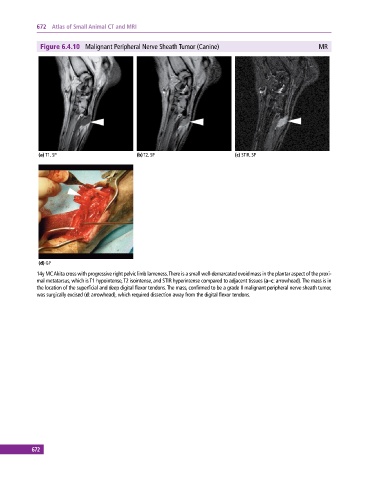

Figure 6.4.10 Malignant Peripheral Nerve Sheath Tumor (Canine) MR

(a) T1, SP (b) T2, SP (c) STIR, SP

(d) GP

14y MC Akita cross with progressive right pelvic limb lameness. There is a small well‐demarcated ovoid mass in the plantar aspect of the proxi-

mal metatarsus, which is T1 hypo intense, T2 isointense, and STIR hyperintense compared to adjacent tissues (a–c: arrowhead). The mass is in

the location of the superficial and deep digital flexor tendons. The mass, confirmed to be a grade II malignant peripheral nerve sheath tumor,

was surgically excised (d: arrowhead), which required dissection away from the digital flexor tendons.